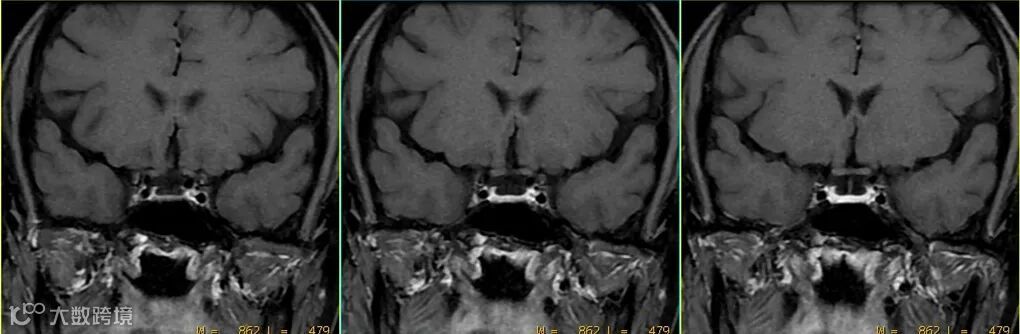

- 但该序列注射对比剂后,横、矢、冠三个方位上血管搏动伪影都非常大,并不利用血管层面及颅底区域病变的显示与判读。如上图△。

- 该序列可以做到增强前后同序列、同层面、同对比,如上图△。这也是很多医院坚持使用该序列增强的原因之一。

- 该序列较2D自旋回波序列,可在一定程度上改善血管搏动伪影。如上图△,该扰相梯度回波T1WI序列上并未见明显血管搏动伪影。

- 但该序列磁敏感伪影较重,图像灰白质对比也不及自旋回波序列,特别是采用压脂后其图像对比明显下降。如上图△,2D T1自旋回波序列与2D T1扰相梯度回波序列的比较。